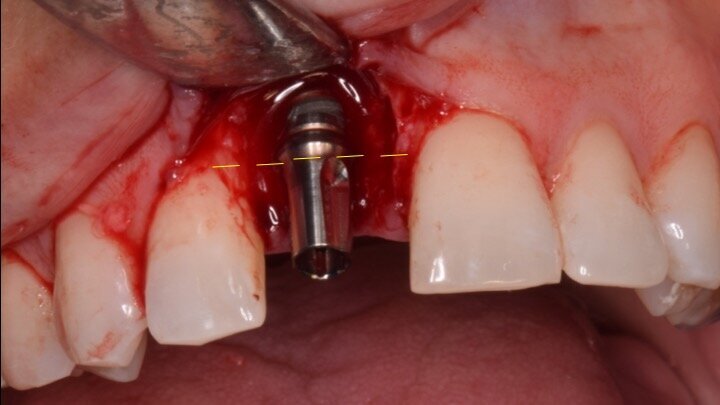

Figura 6. A pesar del defecto óseo, siempre buscamos la posibilidad de crear un nuevo alveolo quirúrgico que emerja por la zona del cíngulo de los dientes adyacentes, es decir, el margen de emergencia adecuado. En estos defectos, intentamos siempre el anclaje en profundidad con implantes largos de unos 16 mm debido al gran defecto existente. Es la única forma de que la estabilidad primaria del implante permita realizar una Prótesis Inmediata.

Figura 7. Implante de conexión interna insertado 2 mm por debajo de la cresta ósea, independientemente del defecto existente y a 55 Nw. Al no existir margen vestibular, tomamos como referencia los dos picos óseos de las papilas y entre ellos trazamos una línea imaginaria que los una enterrando el hombro unos 2 ó 3 mm por debajo de ella.